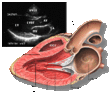

| Each figure contains a TTE with a black background, and a corresponding colored illustration. | Patrick J. Lynch and C. Carl Jaffe, Yale University, 2006. | ||||||||||

| Click on a figure to enlarge it and see some parts of the heart identified. RV, right ventricle; LV, left ventricle; RA, right atrium; LA, left atrium; TV, tricuspid valve; MV, mitral valve; AV, aortic valve; RVOT, right ventricular outflow tract; LVOT, left ventricular outflow tract | |||||||||||